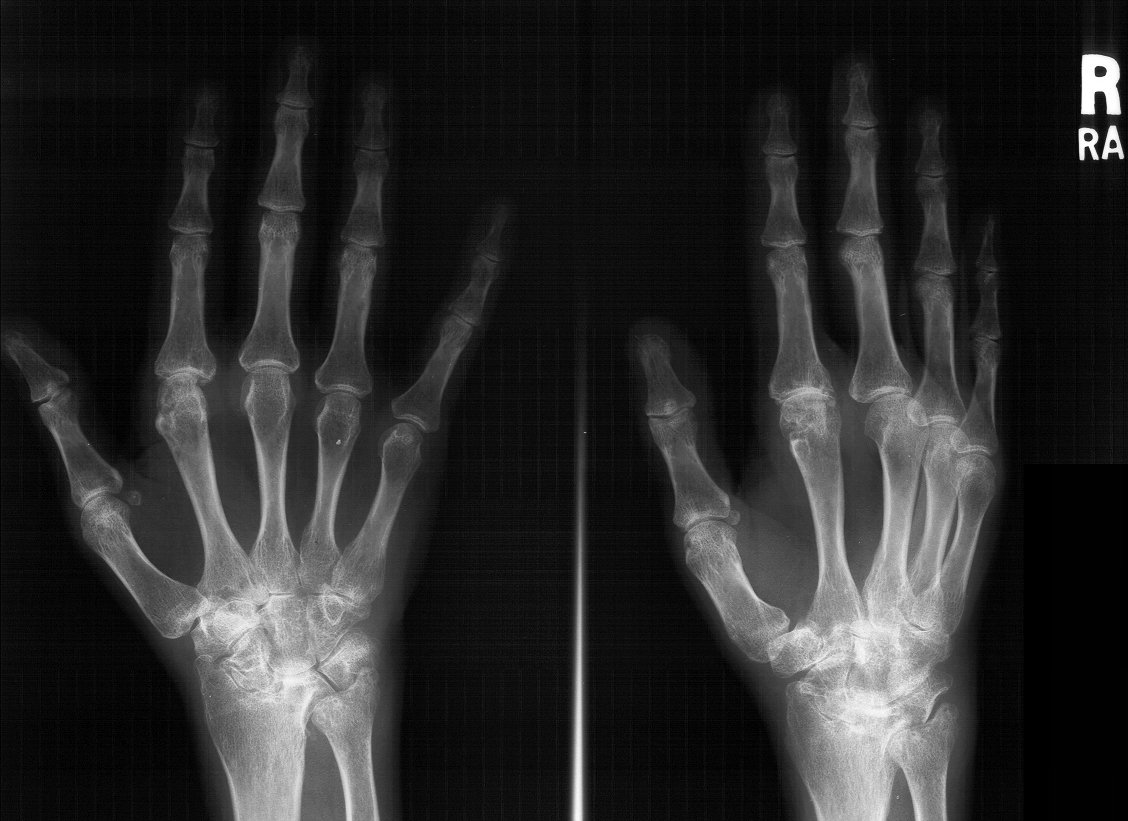

Clinical Example: Rheumatoid arthritis with DRUJ and radiocarpal involvement

Rheumatoid arthritis has many forms of presentation. This patient has bilateral severe radiocarpal and distal radioulnar joint involvement, with relative sparing of the metacarpophalangeal and interphalangeal joints.

The radiolunate joint did not spontaneously fuse on this side, allowing a greater degree of ulnar translation of the carpus. Note the severe cystic carpal changes.